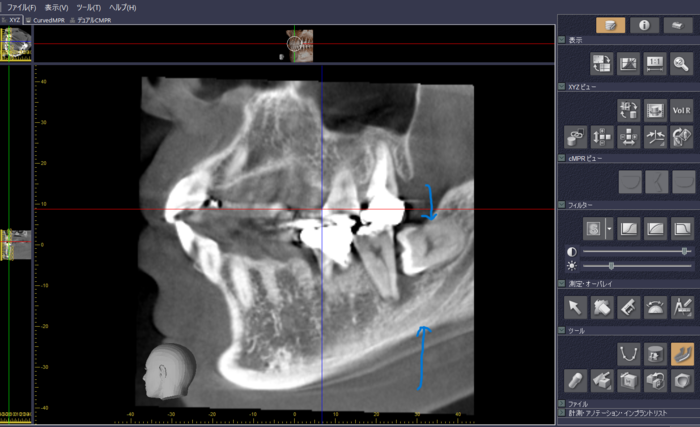

CTを導入して4カ月経ちました。

CT(CBCTと呼ばれます)が、みと歯科・矯正歯科に来たのは、2023年9月11日です。モリタ社製のべラビューエポックスX700+3Dという機種です。モリタは歯科領域で、初めてCTを開発製品化させた会社で、他の製品でもと… [続きを読む]